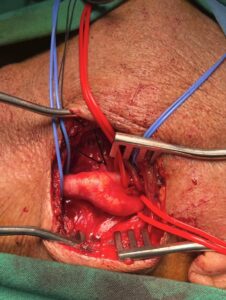

Ανοιχτή αποκατάσταση καρωτιδικής νόσου